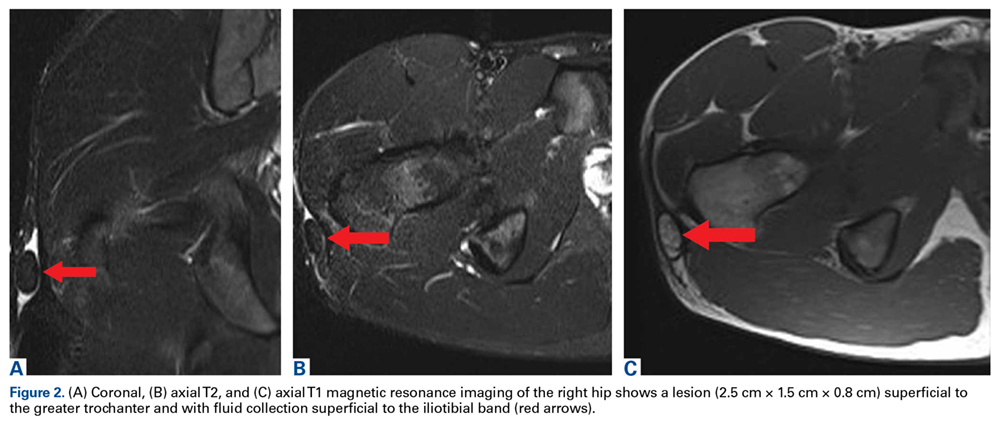

There was tenderness on direct palpation of the mass but no skin changes over it. Magnetic resonance imaging (MRI) showed a discrete fatty mass 2.5 cm × 1.5 cm × 0.8 cm in size (Figures 2A-2C). The subcutaneous mass lay over the iliotibial band and was completely surrounded by a fluid collection.Options discussed with the patient included use of ice, activity modification, and use of protective padded equipment. As the patient had tried these treatments before and was still intermittently having pain with direct pressure, he asked for surgical removal of the mass.